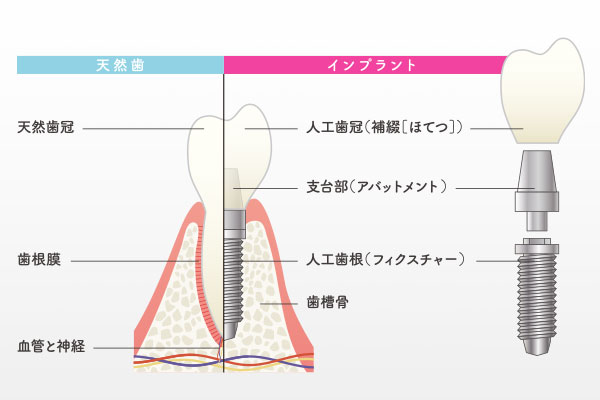

インプラントとは、歯を失った部分の顎の骨にチタン製の人工歯根を埋め込み、その上に被せ物を装着する治療法です。数十年の歴史と確かなエビデンスがあり、骨とインプラントが強固に結合(オッセオインテグレーション)することで、自分の歯のようにしっかりと噛めるようになります。入れ歯のようにガタつくこともなく、見た目も天然歯と遜色ないため、心からの笑顔と食事の楽しみを取り戻すことができます。

インプラントは非常に優れた治療ですが、成功のためには患者さまの協力が不可欠です。特に喫煙はインプラントの成功率・生存率を著しく下げ、インプラント周囲炎のリスクを劇的に高めるため、当院では原則として「禁煙」を条件としています。また、インプラントには天然歯のような歯根のクッション(歯根膜)がないため、噛みすぎて対合する歯を傷めたり、人工物ゆえに感染しやすく、病気の進行が早いため、毎日の正しいブラッシングと定期的なメインテナンスが必須となります。